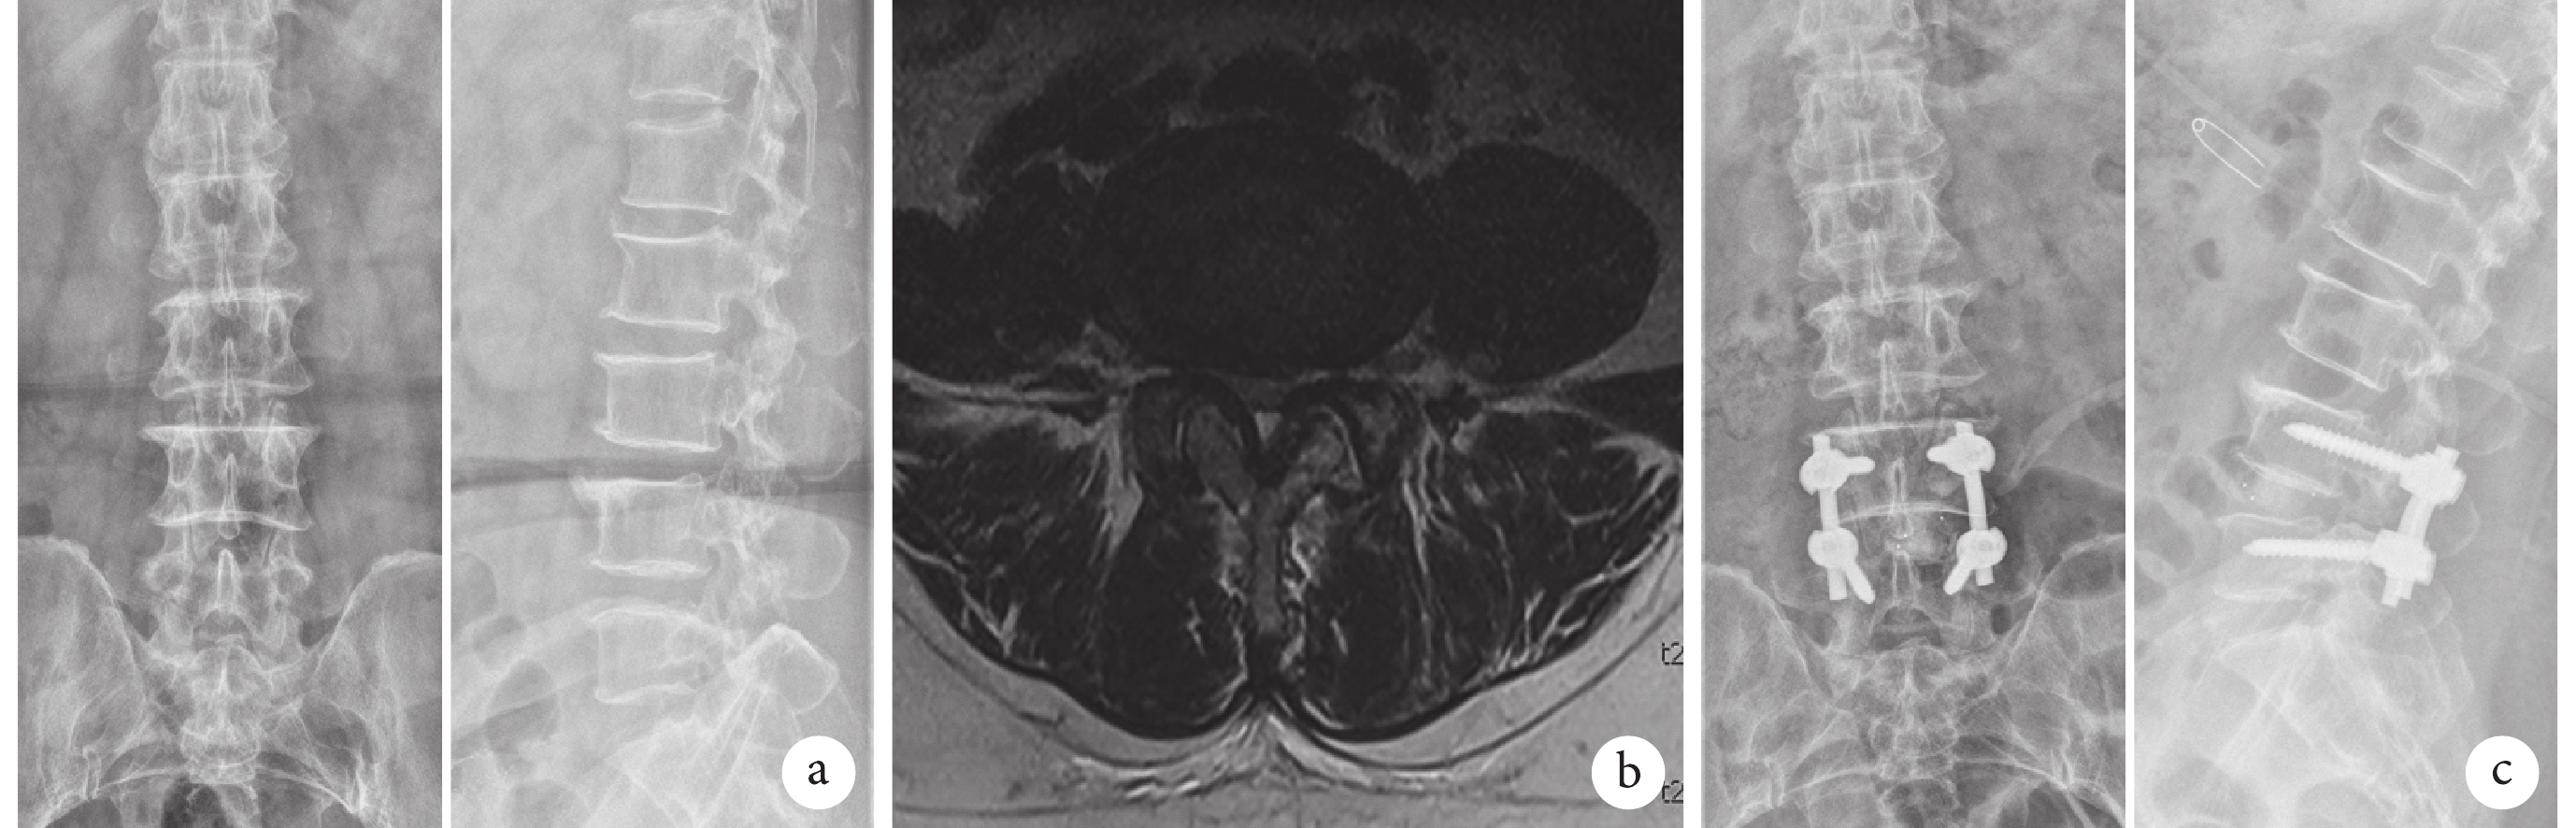

術后影像學復查顯示椎間融合良好。兩組間術前及術后 6 個月 ADH、PDH、SL 比較,差異均無統計學意義(P>0.05);其中,Open-TLIF 組 ADH 及 SL 手術前后差值大于 MIS-TLIF 組,PDH 手術前后差值小于 MIS-TLIF 組,但差異均無統計學意義(P>0.05)。兩組組內術后 6 個月 ADH、PDH、SL 均較術前增加,差異有統計學意義(P<0.05)。見表 2 及圖 1、2。

a. 術前正側位 X 線片;b. 術前 MRI;c. 術后 6 個月正側位 X 線片

Figure1. A 64-year-old female patient with lumbar spinal stenosis at L4, 5 in Open-TLIF groupa. Preoperative anteroposterior and lateral X-ray films; b. Preoperative MRI; c. Anteroposterior and lateral X-ray films at 6 months after operation